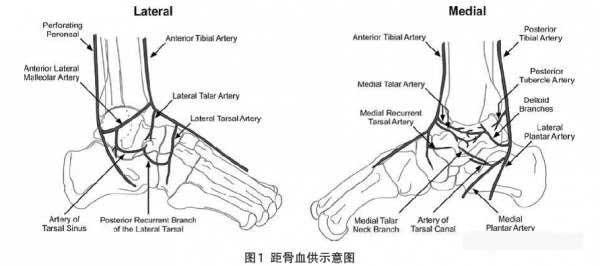

El principal riego sanguíneo del astrágalo proviene de la arteria peronea y la arteria sinusal del tarso, que irrigan la parte inferior del cuello del astrágalo, el astrágalo medial y la mayor parte del cuerpo del astrágalo. La cabeza del astrágalo y el resto del cuello del astrágalo se irrigan a través de la arteria dorsal del pie. La rama calcánea de la arteria tibial posterior también proporciona parte del suministro de sangre al astrágalo. Además, hay muchas ramas anastomóticas entre los vasos del astrágalo para asegurar el suministro de sangre. La investigación de Thomas y Boyce mostró que la arteria tibial posterior suministra el 47% del suministro de sangre al astrágalo, la arteria tibial anterior el 36,2% y la arteria peronea el 16,8%. La arteria tibial posterior irriga todas las partes excepto la parte medial anterior del astrágalo, y la arteria medial anterior proviene principalmente de la arteria tibial anterior. La arteria sinusal del tarso irriga el área lateral de 1/8 a 1/4 del cuerpo del astrágalo, y la arteria del conducto del tarso irriga la mayor parte del cuerpo del astrágalo.